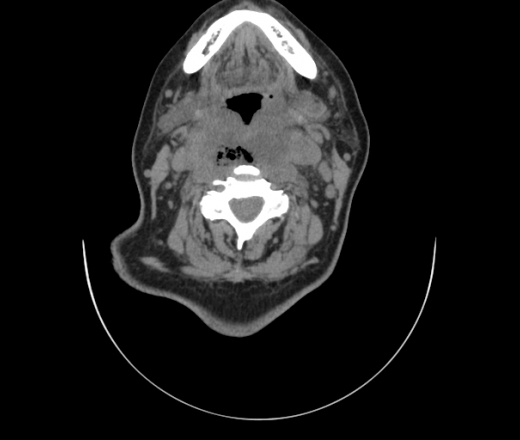

Женщина поступила в х/о спустя 4 дня после того как при употреблении карася подавилась костью.

Наличие газа в средостении на протяжении тел С2-С6 (медиастинальна эмфизема); рыбная кость на уровне тела С6.

При всем уважении, но говорить о медиастинальной эмфиземе, оценивая мягкие ткани шеи, как-то слишком резко. На мой взгляд, это ретрофарингеальное пространство.

Эвакуировали почти 100мл гноя. Но кость не смогли найти. Думаю что она даст дальнейшее ослоднение. Эндоскопически за черпалонадгортаной звязкой не смогли зайти в пищевод, все мягкие ткани отечные, просвет пищевода сдавлен. По всей видимости параэзофагеальная клетчака тоже задействована. Эмпиема, если ее можно так назвать, незнаю как правильно дошла до уровня яремной вырезки. Чем закончиться напишу. Ждем медиастинита.

Флегмона заглоточного пространства шеи, только операция, флегмоны вскрывают. Риск медиастинита.

Согласен с Вами; конечно, наличие газа в клетчатке ретрофарингеального пространства (затмение с опечаткой..). К сожалению, процесс "продвигается" к медиастиниту. Но почему никто, не отмечает наличие рыб. кости; или это для Всех очевидно?

Так вы уже отметили. Хотя ориентировал бы не скелетотопически, а на перстнечерпаловидный сустав.

Кость то мы сразу выявили, размеры где то 17*2мм, но ее так и не получается найти в этой каше